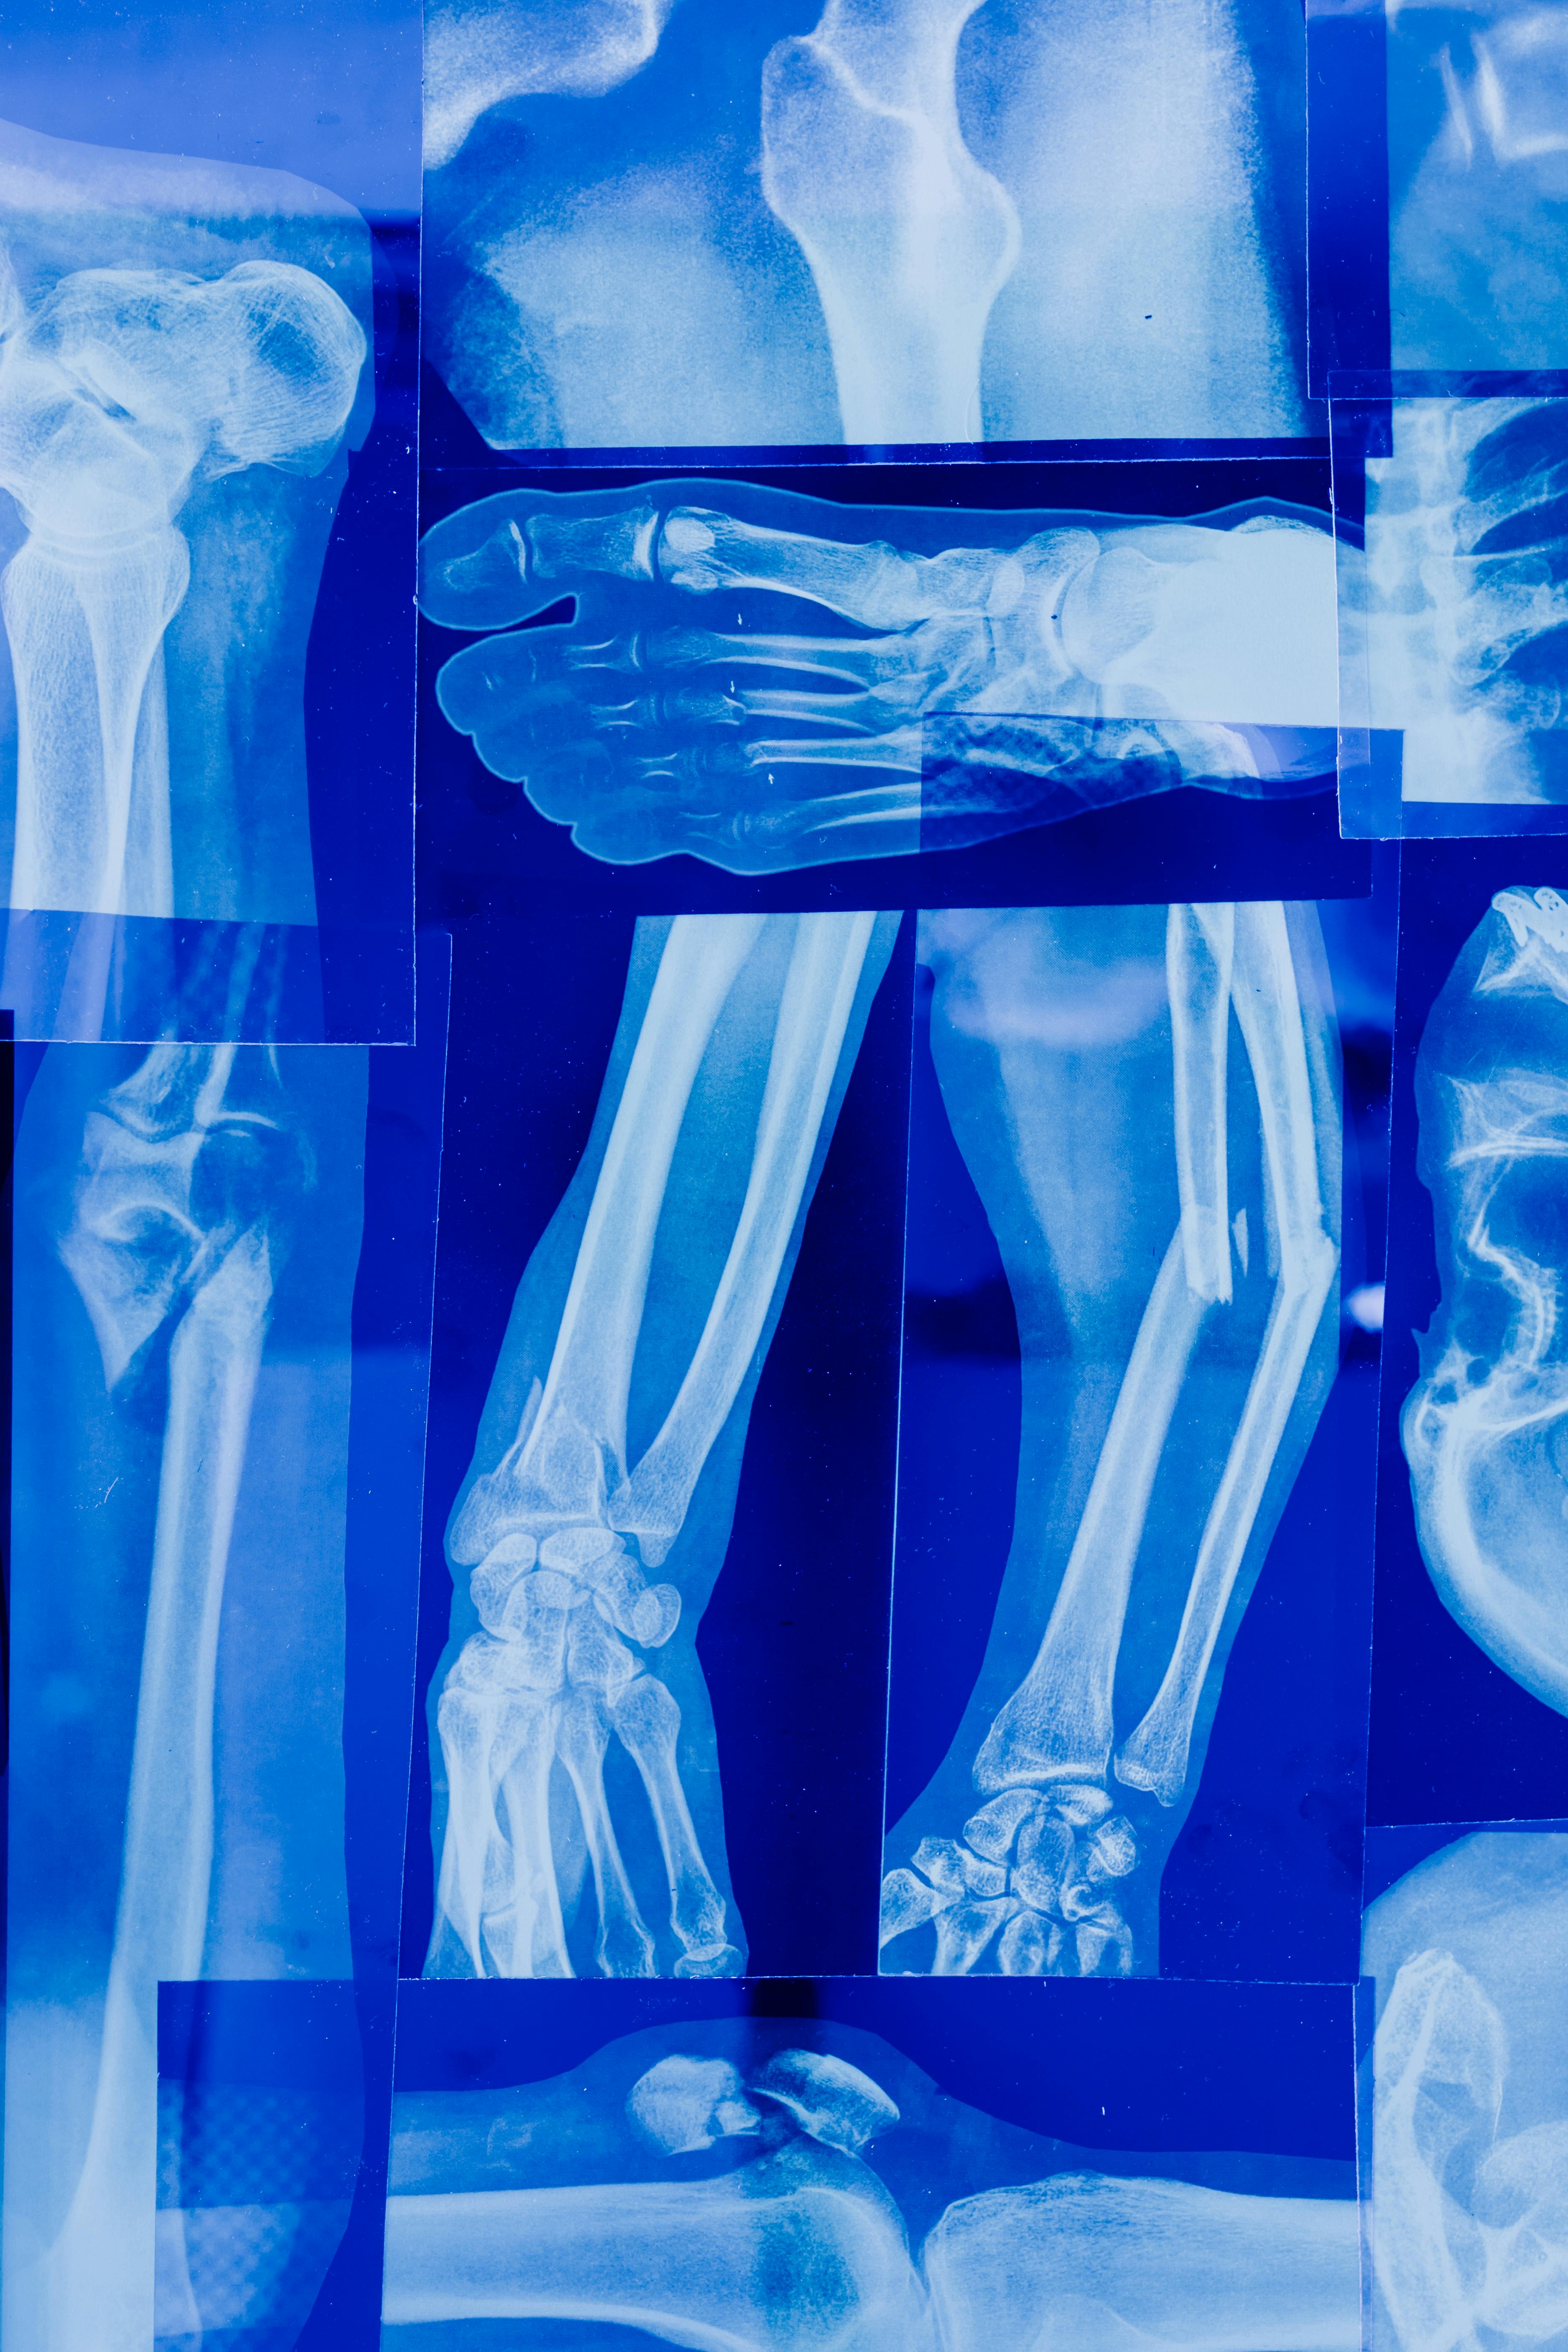

하루 종일 앉아서 일하는 직장인이라면, 어깨가 뻐근하거나 허리가 뻐근했던 경험이 한두 번쯤은 있을 것이다. 손목이 저릿하거나, 목이 뻣뻣해서 고개를 돌릴 때마다 "뚝뚝" 소리가 나기도 한다. "그냥 피곤해서 그런가 보다" 하고 넘기지만, 이런 증상이 계속된다면 근골격계 질환을 의심해봐야 한다.

특히, 요즘처럼 재택근무와 사무직 비중이 늘어나면서 잘못된 자세로 오랜 시간 일하는 사람이 많아졌다. 그러다 보니 목, 어깨, 손목, 허리까지 아프기 시작하는데, 문제는 이렇게 한 번 망가진 몸은 쉽게 회복되지 않는다는 것이다. 그래서 오늘은 직장인들이 흔히 겪는 근골격계 질환의 증상과 원인, 그리고 이를 예방하는 방법까지 알아보려 한다.

직장인에게 흔한 근골격계 질환, 내 몸은 괜찮을까?